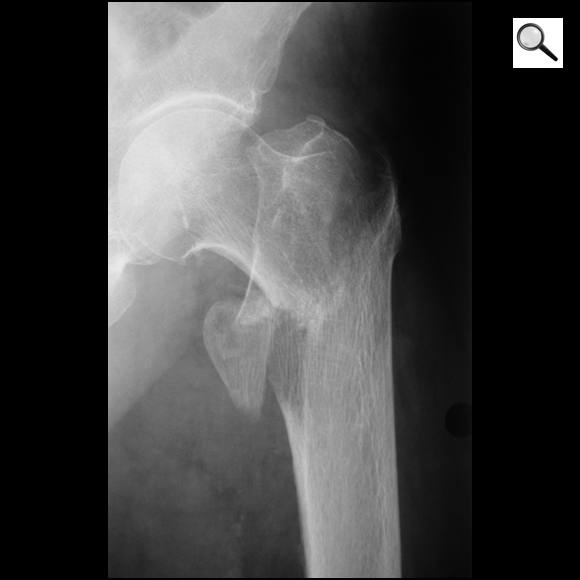

Q

Quel est le stade Garden de cette fracture de l’ES du fémur? Quel est le risque évolutif principal?

Fracture ES fémur garden 4 car perte de contact entre fragments,

les travées osseuses sont normales

Risque max d’ostéonécrose aseptique